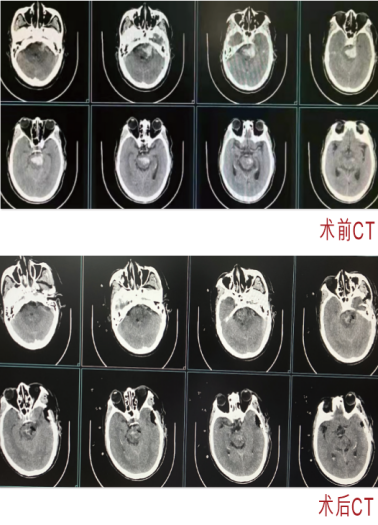

脑干血肿清除术

脑出血,通常指的是自发性脑出血,具有高死亡率、高花费及高致残率,其中高血压性脑出血发病率最高,而脑干出血是高血压脑出血中最严重,致死及致残率最高的。大脑是人体的司令部,而脑干是生命中枢所在,地位及功能极其重要,一旦发生出血,可以说是九死一生。针对脑干出血的治疗,神经外科积极向国内大型医院看齐,利用神经内镜微创技术,开展脑干血肿清除术,取得一定的效果,使得病人的生存率有所提升。通过该技术的应用,我院在脑干血肿清除术方面在柳州市内取得领先地位,手术量为柳州市第一。